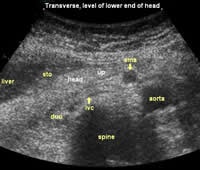

The following study describes anatomical landmarks in the ordinary pancreas of a thin patient:

Transverse planes in caudal direction:

![]() Image03 |